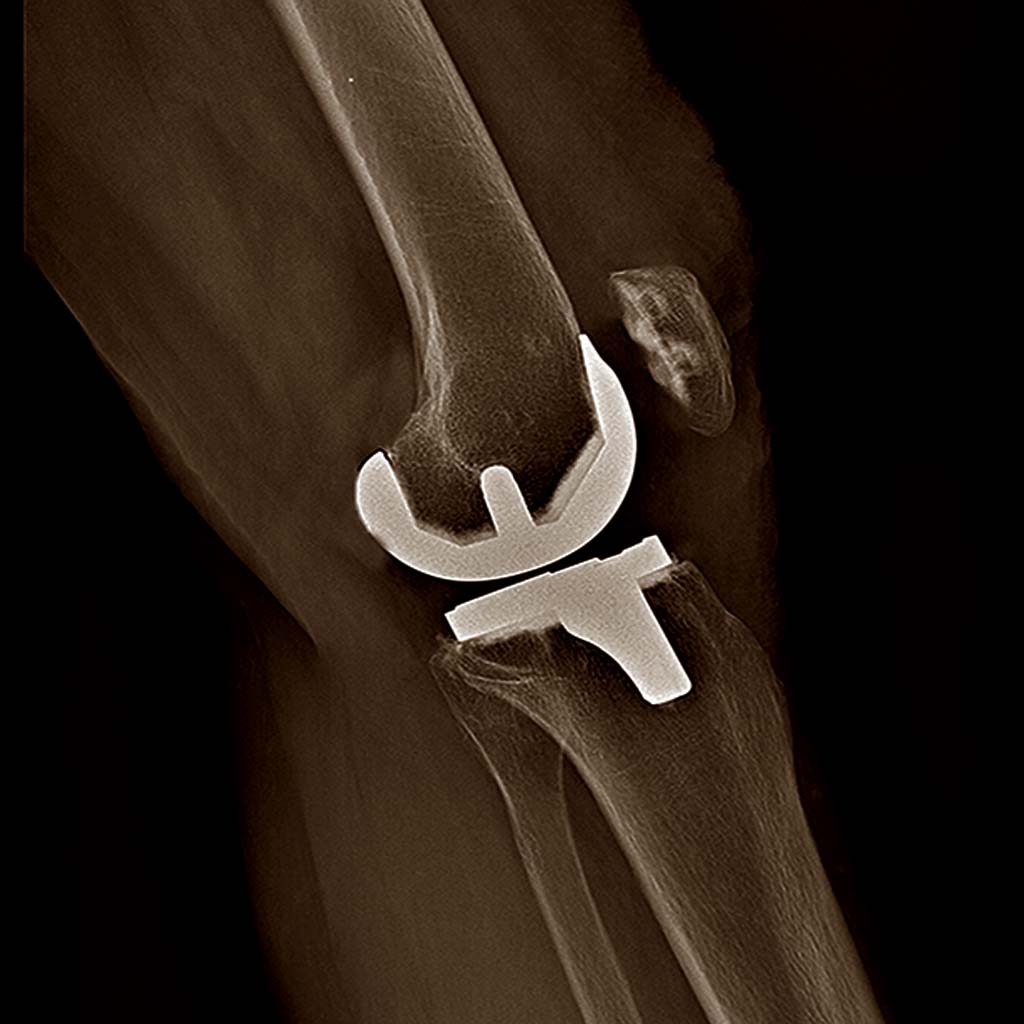

#RDVORTHO N°2 : Qu’est-ce que l’arthrose ?

Série de Podcasts sur la Chirurgie orthopédique créée par le Dr Benjamin GUENOUN, chirurgien orthopédiste...

Lire la suite →